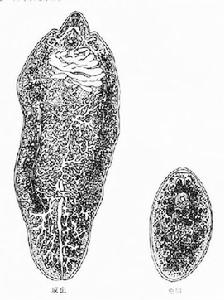

形態

肝寄生蟲肝片形吸蟲與薑片蟲同屬片形科(Fasciolidae),是大型吸蟲之一。其薑片蟲的不同點有:1)成蟲較狹長,體前端有一錐形突起稱頭錐;2)腹吸盤較小,不甚明顯,位於頭錐基部水平;3)腸支有許多側分支;4)睪丸兩個,分支很細,約占蟲體面積二分之一;5)卵巢較小,分枝細。

成蟲體形狹長,背腹扁平,前端稍窄,後端鈍圓,狀似葵花子,體表無棘。蟲體大小一般為10~25×3~5mm。口吸盤略大於腹吸盤,前者位於體前端,後者位於蟲體前1/5處。消化道簡單,口位於口吸盤的中央,咽呈球形,食道短,其後為腸支。腸支分為兩支,沿蟲體兩側直達後端,不匯合,末端為盲端。排泄囊為一略帶彎曲的長袋,前端到達受精囊水平處,並向前端發出左右兩支集合管,排泄孔開口於蟲體末端。雄性生殖器官有睪丸1對,前後排列於蟲體後部1/3,呈分支狀。兩睪丸各發出1條輸出管,向前約在蟲體中部匯合成輸精管,通儲精囊,經射精管入位於腹吸盤前緣的生殖腔,缺陰莖袋、陰莖和前列腺。雌性生殖器官有卵巢1個,淺分葉狀,位於睪丸之前,輸卵管發自卵巢,其遠端為卵模,卵模周圍為梅氏腺。卵模之前為子宮,盤繞向前開口於生殖腔。受精囊在睪丸與卵巢之間,呈橢圓形,與輸卵管相通。勞氏管位於受精囊旁,也與輸卵管相通,為短管,開口於蟲體背面。卵黃腺呈濾泡狀,分布於蟲體的兩側,兩條卵黃腺管匯合後,與輸卵管相通。

蟲卵形似芝麻,淡黃褐色,一端較窄且有蓋,卵蓋周圍的卵殼增厚形成肩峰,另一端有小瘤。卵甚小,大小為27~35μm×12~20μm。從糞便中排出時,卵內已含有毛蚴。